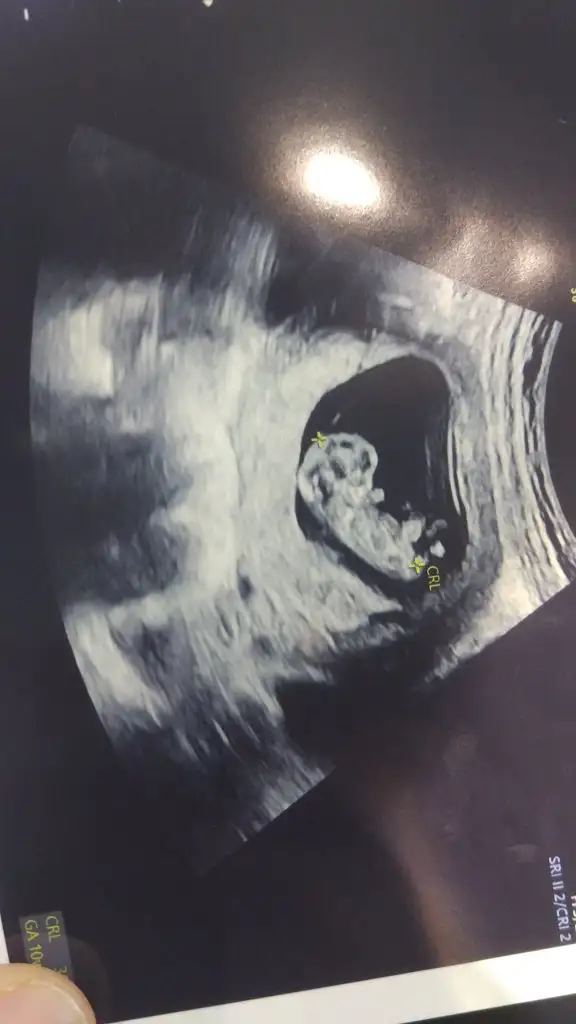

Bence erkek gibi duruyor saglikli olsun da İNSAALLAH ALLAH gönlündekini versinMerhaba kızlar ben de kontrolden geldim çok şükür her şey yolunda fakat kanama alanından ötürü iki hafta rapor verecek doktorum. Pazartesi itibariyle başlamadan rapor almış olacağım. Cinsiyet tahmini yapabilecek olanları beklerim

Maşallah çok tatlıArkadaslar sukur iyi. Ama risk oldugu icin progestan basladi. Sizce benimki kiz mi erkek mi

ALLAH saglikla gelişmesini kucagina almasını nasip etsin İNSAALLAH canim erkekArkadaslar sukur iyi. Ama risk oldugu icin progestan basladi. Sizce benimki kiz mi erkek mi

Gecmis olsun , bol bol dinlenecegin bir surece giriyorsumMerhaba kızlar ben de kontrolden geldim çok şükür her şey yolunda fakat kanama alanından ötürü iki hafta rapor verecek doktorum. Pazartesi itibariyle başlamadan rapor almış olacağım. Cinsiyet tahmini yapabilecek olanları beklerim

Çok sevdim yorumunuBence bu kız maşallah

Aminn canım bir oğlum var hangisi olursa çok sevinirim tabi ama bir de kız neden olmasınBence erkek gibi duruyor saglikli olsun da İNSAALLAH ALLAH gönlündekini versin

Bence erkekArkadaslar sukur iyi. Ama risk oldugu icin progestan basladi. Sizce benimki kiz mi erkek mi